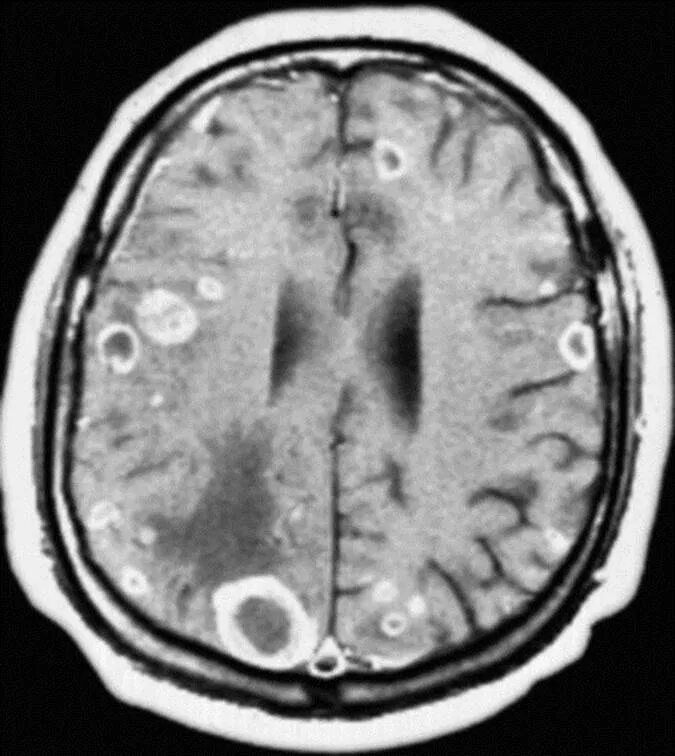

Отек мозга метастазы